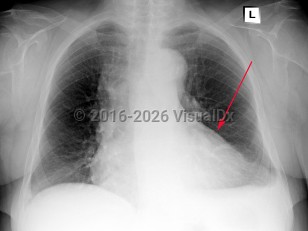

Congestive heart failureCongestive heart failure

Pulmonary hypertension

Cor pulmonale